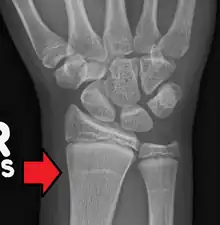

| Growth arrest lines in a child with an underlying bone disease | |

Growth arrest lines, also known as Harris lines, are lines of increased bone density that represent the position of the growth plate at the time of insult to the organism and formed on long bones due to growth arrest. They are only visible by radiograph or in cross-section. The age at which the lines were formed can be estimated from a radiograph. Harris lines are often discussed as a result of juvenile malnutrition, disease or trauma. Other studies suggest a reconsideration of Harris lines as more of a result of normal growth and growth spurts, rather than a pure outcome of nutritional or pathologic stress.[1] The lines are named after Henry Albert Harris (1886–1968), professor of anatomy at the University of Cambridge.[2]

Particularly, deficiencies in protein and vitamins, which lead to delayed longitudinal bone growth, can result in the formation of Harris lines.[3] During the process of endochondral bone growth, the cessation of osteoblastic activity results in the deposition of a thin layer of bone beneath the cartilage cap, potentially forming Harris lines.[4][5] Subsequent recovery, necessary for the restoration of osteoblastic activity, is also implicated in Harris line formation.[6] When matured cartilage cells reactivate, bone growth resumes, causing a thickening of the bony stratum. Therefore, complete recovery from periods of chronic illness or malnutrition also manifests as transverse lines on radiographs. Lines tend to be thicker with prolonged and severe malnutrition. Harris line formation typically peaks in long bones around 2–3 years after birth and becomes rare until adulthood after the age of 5. Additionally, Harris lines occur more frequently in boys than in girls.[7]